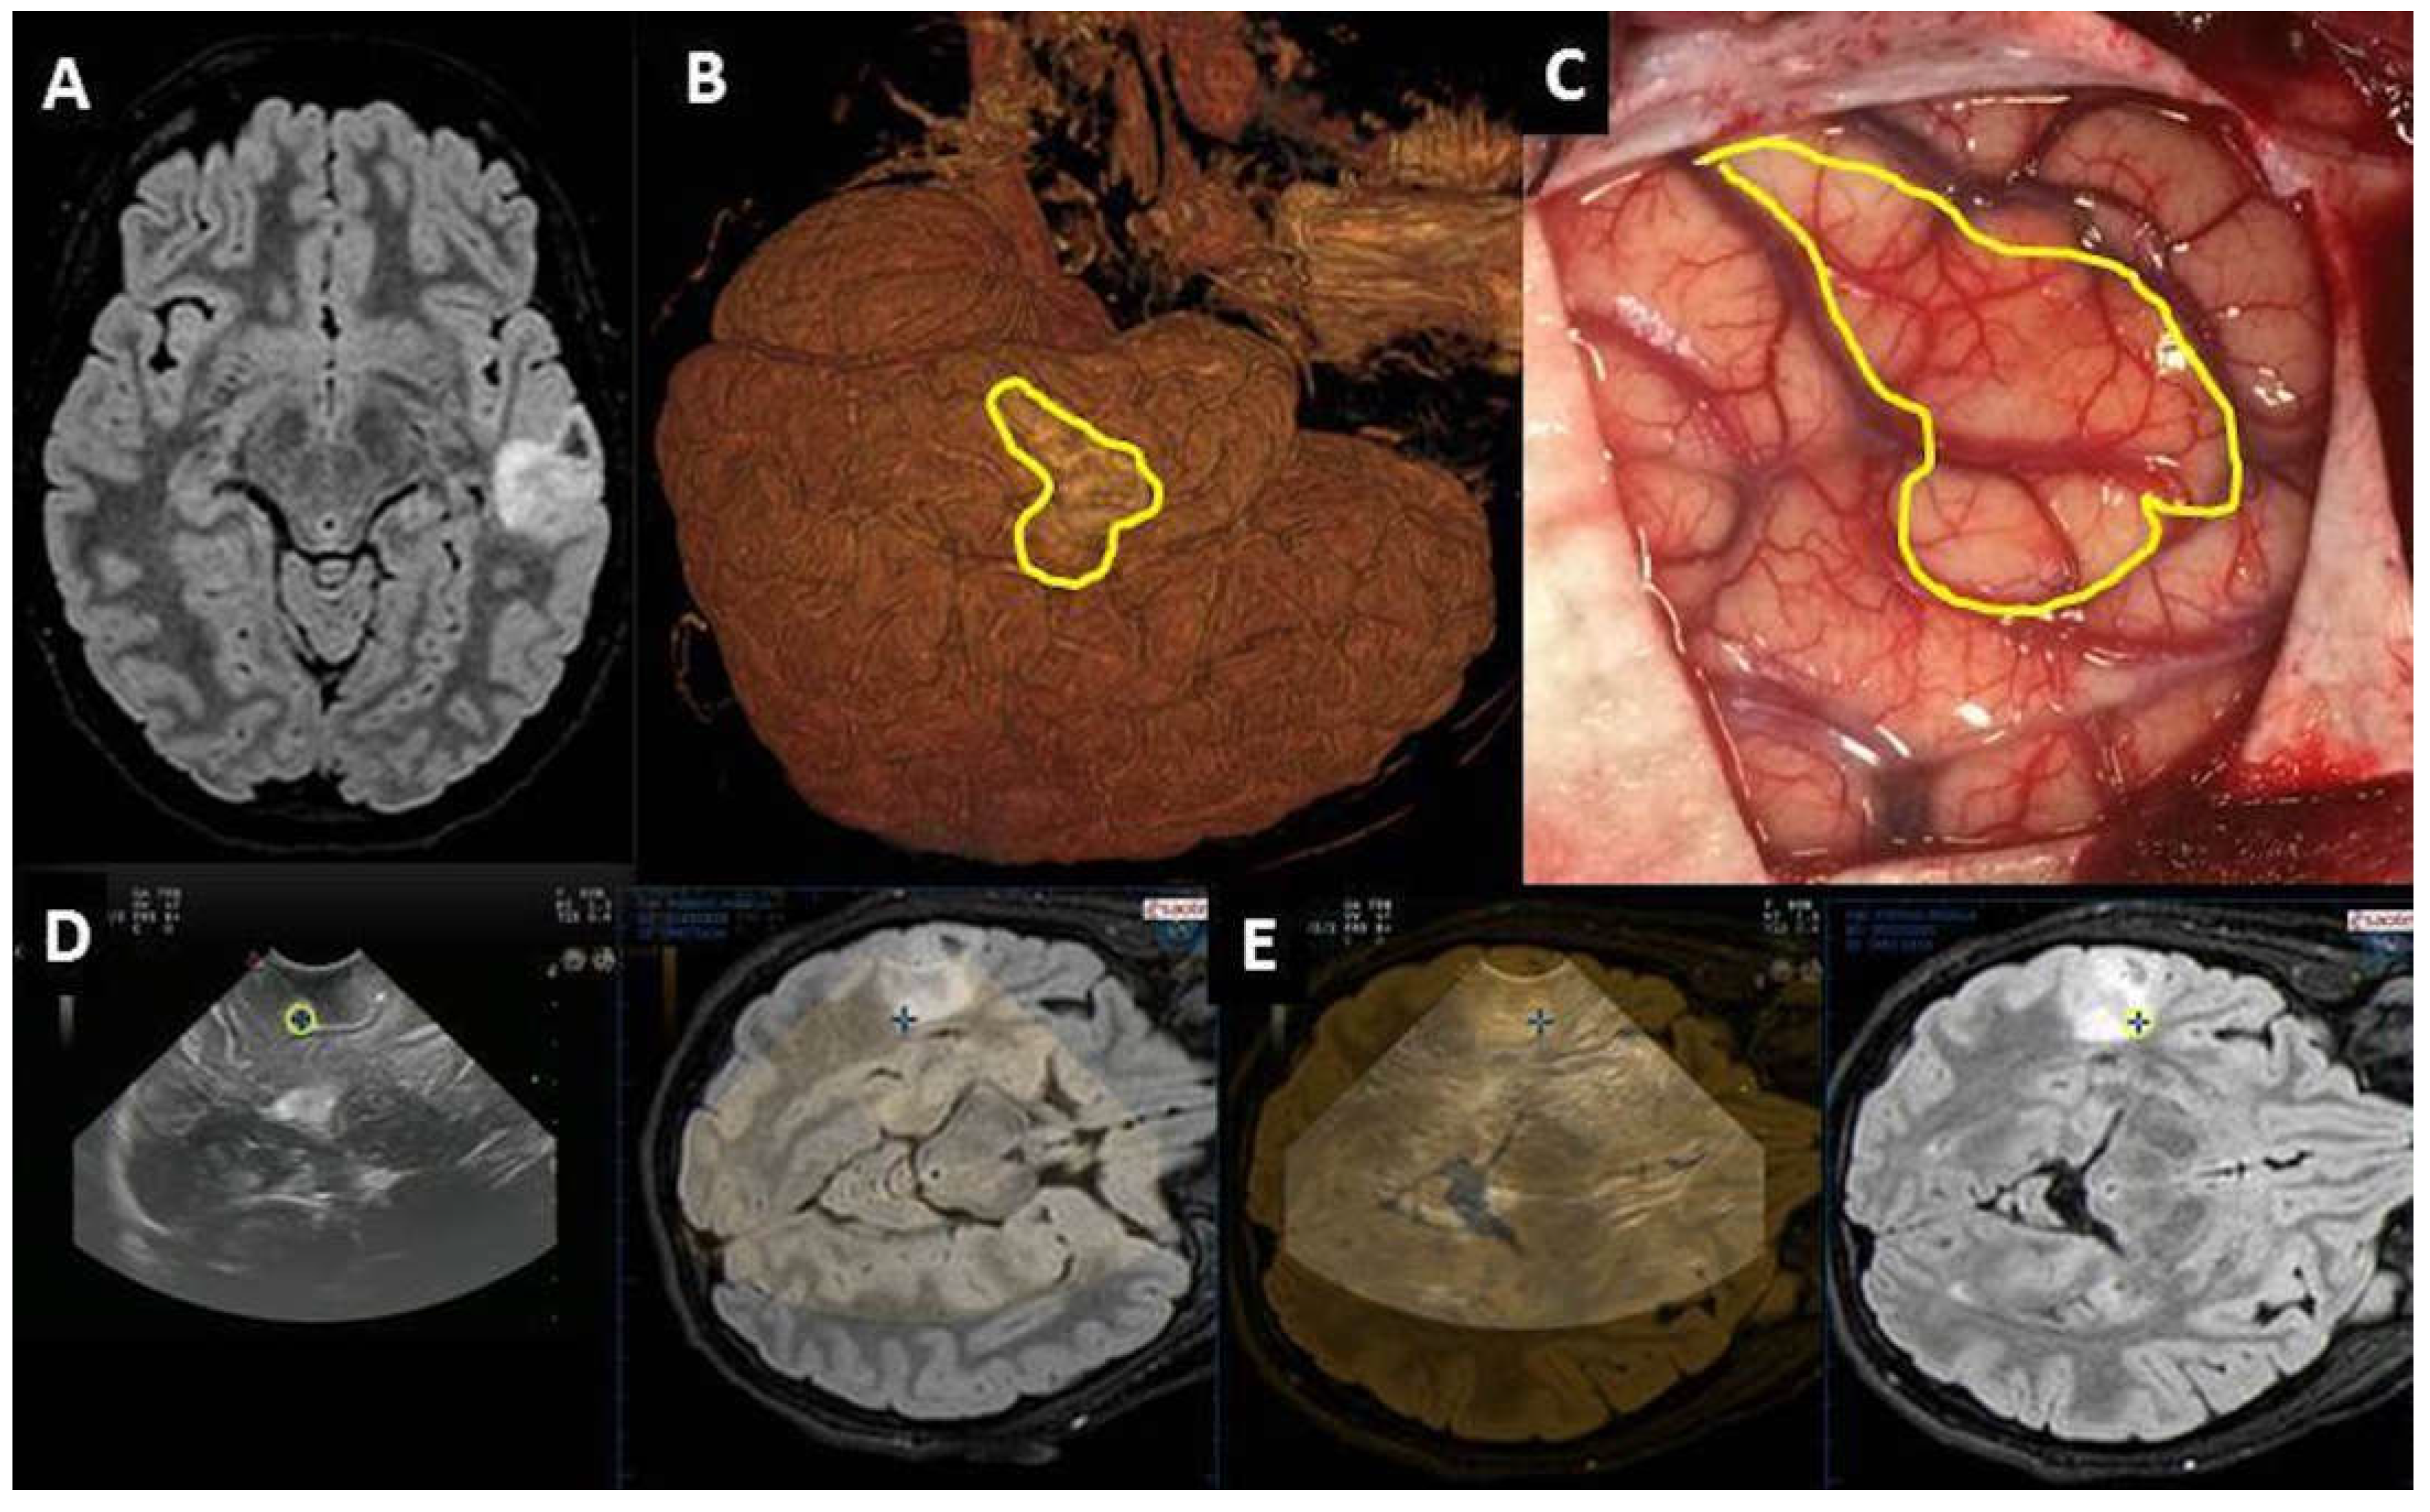

| Pre-IOUS | Problems | Solutions |

|---|---|---|

| Localization | Deep-seated lesion |

|

| Localization | Superficial lesion not distinguishable from brain parenchyma |

| Definition | Vascular relationship |

| Definition | Vascular pattern |

| Surgical route | Deep-seated lesion |